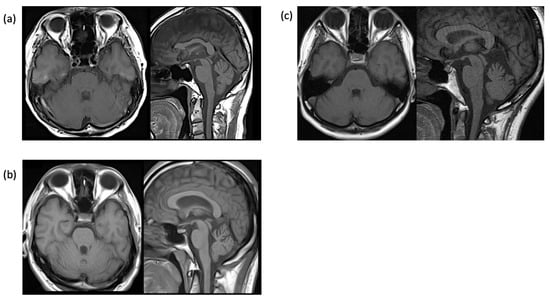

At the age of 60 years, the incidence of attacks increased to 2–3 per week and lasted 1–5 h; he revisited our clinic with a referral from another hospital. The electroencephalogram (EEG) revealed intermittent delta waves in the bilateral frontal–temporal regions. The head MRI showed mild cerebellar atrophy (Figure 2a), but the brain SPECT did not show cerebellar hypoperfusion. Whole-exome sequencing identified a previously reported two-base deletion variant (NM_001127222.2: c.2039-40 del AG, p.Q680R fs*16) [10] (Figure 3a). The patient was diagnosed with EA2, levetiracetam was added to acetazolamide starting at 250 mg and then increased to 750 mg, attacks decreased to once every 2 to 3 weeks (Figure 4a), and the duration slightly shortened to 0.5 to 2 h. Currently, attacks occur once every 1–2 weeks and last from 1.5 to 6 h. The effect of levetiracetam was stable for seven years.

He was referred to our department after resuming treatment with zonisamide 200 mg/day. Neurological examination revealed gaze nystagmus while looking to the left, but no other abnormalities. The head MRI was normal, and EEG showed frequent bilateral frontal spikes and waves. At the age of 30, he stopped taking his medication and visiting our hospital, but at the age of 31, he returned to the hospital because of unsteadiness lasting 1–1.5 h every morning. MRI showed mild cerebellar atrophy (Figure 2b), and brain SPECT showed mild cerebellar hypoperfusion predominantly in the left side. EEG revealed spike and wave complexes and intermittent theta waves in the bilateral frontal regions. Genetic testing with informed consent showed that the number of CAG repeats in the CACNA1A gene was within the normal range of 12/13, but whole-exome sequencing identified a novel nonsense variant of the CACNA1A gene (NM_001127222.2: c.5505 G>A, p.W1835*) (Figure 3b). The same variant was found in his mother and sister. He was diagnosed with EA2 and started acetazolamide 500 mg/day at 32 years of age.

A 46-year-old woman presented with episodic ataxia during sitting and walking, with a frequency of approximately once a month since the age of 24 years, which improved within 2 to 3 h. She tended to have attacks when under mental stress. There was no family history as shown in the family tree (Figure 1c). At 27 years of age, her attacks increased to about once a week, and she was admitted to the Department of Neurology, Jichi Medical University Hospital, for a thorough examination [11]. On admission, neurological examination revealed no nystagmus or other neurological findings during the interictal period. During hospitalization, three attacks occurred. During the attacks, bilateral gaze nystagmus, slurred speech, truncal ataxia, and gait instability were observed, and the symptoms persisted for about 2.5 h. Blood, cerebrospinal fluid, and electroencephalography findings were normal, and head MRI revealed a mildly enlarged folia on the superior cerebellar vermis (Figure 2c). Brain SPECT showed no cerebellar hypoperfusion, and 1H-MR spectroscopy showed a decreased NAA/Cr ratio in the cerebellar hemispheres. Informed consent was obtained for genetic testing of CACNA1A, which showed no pathologic nucleotide substitutions, but CAG repeats were expanded to 22/13. The patient was diagnosed with SCA6 with episodic ataxia.

Figure 2. Brain MRI findings of the three patients. (a) Case 1, (b) Case 2, (c) Case 3. T1-weighted axial and sagittal images show mild upper cerebellar vermian atrophy.